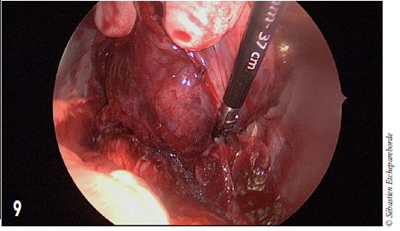

photo 3

Photo 3 - Échographie

À l’échographie, la masse présente quelques cavités kystiques bien que le reste du parenchyme soit assez homogène.